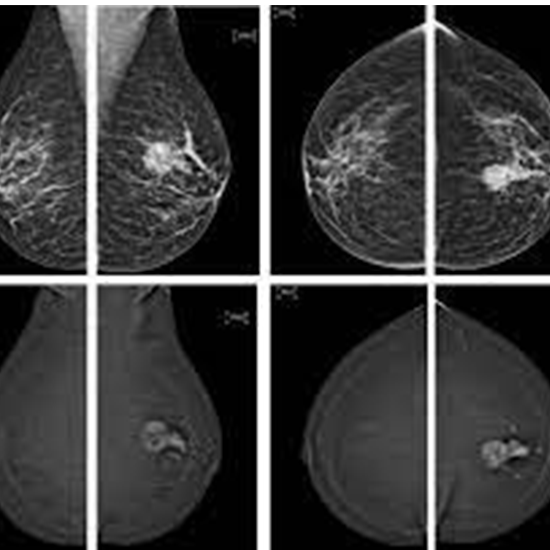

An MRI breast scan is performed to check for breast cancer or any other abnormalities in your breast.

To check the cancerous cells in your breast if that is growing or any structural abnormalities that are causing any problem in the layers of the breast.

But, unlike mammography, which utilizes X-rays to take pictures of the breast, MRI involves magnets and radiofrequency to obtain precise 3-dimensional imaging of the breast tissue. You will require to have a contrast fluid (dye) put into your forearm via an intravenous line prior to the procedure.